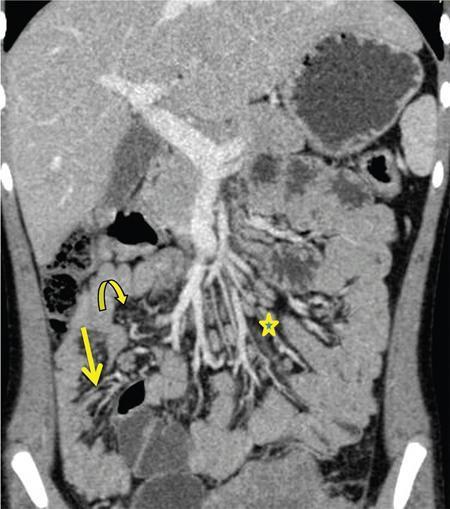

Neera Kohli, Anit Parihar Objectives: To provide the readers with a comprehensive, simplified, lucid, well-illustrated and well-presented latest account of the anatomy, functions, and childhood diseases of the mesentery. Key terms: Mesentery, anatomy, functions, infections, inflammation, neoplasia, cysts, malrotation, vasculitis, textiloma, hernias. Learning objectives: To approach a clinical condition of the mesentery in a logical and comprehensive manner so as to help the patient maximally. Increasing number of researchers, anatomists, radiologists, treating physicians and surgeons are now considering the mesentery as a separate organ. Serious attempt has been made by the authors to stick to the new theory while choosing and describing the various paediatric diseases to be included in this chapter. Likewise, each condition has been described as inclusively as possible. Mesentery develops from the splanchnic mesoderm. It has two parts: a ventral part that forms the mesentery of the abdominal part of oesophagus, the lesser omentum and mesentery of the first part and proximal half of the second part of the duodenum. The other is the dorsal part that runs below the diaphragm, from the oesophagogastric junction to the anorectal junction forming the mesentery of rest of the gastrointestinal tract (GI) including the greater omentum. It consists of fat, and has blood vessels, nerves and lymphatics running that supply the GI. Interest in the mesentery was reactivated when Heald in 1988 demonstrated that tumour recurrence following rectal cancer surgery was dramatically decreased if the mesorectum was removed. Heald’s work was the true start of mesenteric-based surgery. Hohenberger in 2009, focused on the mesocolic region, and showed that intestinal tumour recurrence was minimized, if the mesocolon was surgically excised intact. Heald and Hohenberger thus prompted a renaissance in the study of the mesentery and abdominal anatomy. Following their findings, research was done which demonstrated that the mesentery below the duodenum is continuous, and that the large and small intestine is centrally connected to the rest of the body, by the mesentery. Mesentery originates or has root posteriorly, at the level of origin of the superior mesenteric artery (SMA), as these findings clarified its shape, they marked the start of the scientific study of the mesentery and led to the proposal that it be reclassified an organ. Subsequent research showed that abdominal digestive organs, that is, liver, spleen, intestine and pancreas develop either on or in it. This relationship is retained into adulthood, so abdominal digestive organs are directly connected to the mesentery or we can say that they are ‘mesenteric’ in embryological origin and anatomical position (Fig. 7.10.1). Accordingly, all abdominal and pelvic organs belong either to a mesenteric or a non-mesenteric domain. This model explains the positional anatomy of all abdominal digestive organs and associated vasculature. Moreover, it explains the peritoneal landscape and enables differentiation of peritoneum from the mesentery. Hence, the mesentery should be subjected to the same investigatory focus that is applied to other organs and systems. One should be well versed with the normal appearances of mesentery on USG, CT and MRI (Fig. 7.10.2 A–C). Wherever mesentery is attached, a fascia (Toldt’s fascia) runs between the mesentery and the abdominal wall. This mechanism of anchorage is important. Second mechanism of anchorage involves the peritoneum which lines the abdominal wall and is reflected onto viscera as the ‘peritoneal reflection’. The mesentery, Toldt’s fascia, and peritoneal reflection are continuous. The third mechanism of anchoring is the vascular pedicle. Further mesenteries may be divided into true and specialized mesenteries. True mesenteries connect abdominal organs to the posterior wall of the abdominal cavity. These are the small bowel mesentery, the transverse mesocolon, and the sigmoid mesentery. Rest are specialized mesenteries. They do not attach organs to the posterior wall of the abdomen. The mesenteric organ is responsible for the development of systemic inflammation, such as the systemic inflammatory response syndrome (SIRS) and multiple organ dysfunction syndromes (MODS). Proinflammatory cytokines are produced in the intestine and mesentery and are then systemically distributed via mesenteric lymph. These contribute to a systemic inflammatory response, for example, post injury. The mesentery comprises a connective tissue lattice within which adipocytes are present in large numbers. Due to production of cytokines like C-reactive proteins (CRP), resistin, leptin and adiponectin by the mesentery it is considered responsible for glycemic/lipidemic disorders. Mesentery is a big source of secretion of CRP as it contains the largest part of visceral fat hence it is being implicated in diabetes and metabolic syndrome, suggesting that mesenteric adipocytes play a role in the pathobiology of these disorders. Further, visceral tissue plays an important role in immune regulation and may function as a proinflammatory agent. In mesenteric inflammation, both tissue and circulating fibrocyte levels are elevated and are associated with autoimmunity (e.g. systemic scleroderma, rheumatoid arthritis, Grave’s disease), inflammation, and fibrosis (idiopathic pulmonary fibrosis). These can differentiate into adipocytes or fibroblasts and are associated with autoimmunity in conditions such as: systemic scleroderma, rheumatoid arthritis, Grave’s disease and idiopathic pulmonary fibrosis. Fibrocytes also have the ability to act as proinflammatory cells by secreting cytokines. Although currently neutrophils, lymphocytes, adipocytes, and fibrocytes are being studied in details, it is quite possible that there are other varieties of cells involved in mesenteric inflammation. ANML, also known as primary mesenteric lymphadenitis, is a self-limiting inflammatory disease of the mesenteric lymph nodes of right lower quadrant. Clinically it closely resembles acute appendicitis (AA). It occurs in children, adolescents and young adults. CRP and leukocyte count do not help much in differentiating these two conditions. Ultrasonography is the investigation of choice for diagnosing ANML. If three or more mesenteric lymph nodes with a short-axis diameter of 8 mm or more without any associated inflammatory process is identified then ANML is a strong possibility (Fig. 7.10.5A and B). CT if needed, is usually reserved for older patients. Radiologists should try to visualize the appendix as well. If the appendix is normal then it favours diagnosis of ANML. Occasionally, very large mesenteric lymph nodes may result in vascular compromise leading to ischemic colitis. Secondary mesenteric lymphadenitis is associated with some detectable intraabdominal inflammatory process. ANML is more common than AA in the first decade of life. AA becomes more frequent in the second decade and is distinctly uncommon after the age of 20. Boys are more commonly affected. Common symptoms are: fever, vomiting, change in consistency and frequency of stools and mild pain to severe colic. The pain mimics that of AA as it is felt in the right iliac fossa as well as in the periumbilical area. Although, this condition is referred to as nonspecific yet causative micro-organisms have been identified. These are: Several viruses, Yersinia enterocolitica, Helicobacter jejuni, Campylobacter jejuni, Salmonella spp., Shigella spp. and Mycobacterium tuberculosis. Yersinia enterocolitica is considered the most common pathogen in temperate regions. It has been observed that, when ANML or appendicitis occurs in childhood or adolescence, there is a significantly reduced risk of ulcerative colitis later in life. CD is a chronic inflammatory disease that affects the GI and adjacent mesentery in the paediatric and adult populations. Its prevalence is increasing worldwide. Mesentery of patients with CD has more fat tissue. These fat cells can produce proteins such as CRP which is associated with inflammation. This may be the cause of increased inflammation and bacterial invasion. Imaging studies have very vividly shown mesenteric and intestinal involvement in CD. Following are the findings noted in CD of the mesentery: Increased vascularity, oedema, lymphadenopathy, proliferation of the fibrous and fatty tissue, and increased density of fat. Besides these, stenosis and sacculations in the mesentery are also seen. Computed tomography (CT), magnetic resonance (MR) enterography, and strain elastography findings are demonstrated equally well in the mesentery and contiguous intestine. CT enterography is a better modality for assessing mesenteric abnormalities. Sakurai et al. have demonstrated radiological evidence of mesenteric hypervascularity (‘comb sign’) and nodal enlargement correlated with endoscopic evidence of mucosal ulceration. Gale et al. compared MR and CT enterography findings in 84 children and adolescents having active CD with radiological findings in their mesentery. They concluded that mesenteric hypervascularity, oedema, fibrofatty proliferation and lymphadenopathy correlated well with active mucosal disease. Mesenteric vascular diseases like arterial emboli, venous thrombi, and venous congestion have been reported in CD. These may be complicated by bowel ischemia and perforation. Lymphoma may arise in the mesentery in CD, without involvement of other organs, so neoplasia must be considered as a differential of a mesenteric mass arising in CD. It was first reported as retractile SM in 1924. SM is a rare, benign idiopathic, chronic, fibroinflammatory disease of the small bowel mesentery. It is of three types: mesenteric lipodystrophy, mesenteric panniculitis and retractile mesenteritis. Prevalence of mesenteric panniculitis is 0.6%. All three have distinct radiographic features, however, there is considerable overlap. Mesenteric panniculitis (MP) is a localized, chronic inflammatory process, seldom advancing to become fibrosis which may be florid. SM on sonography is seen as a hyperechoic, vessel encasing mass. This mass can also cause adjacent bowel displacement. This same feature is seen as halo sign on CT but without occlusion. CT can also show significant lymphadenopathy, bowel displacement and increase in the enhancement of surrounding fat labelled as ‘misty mesentery’, which is characteristic of MP. These findings are useful in differentiating SM from lymphomas and desmoids. The soft tissue nodules and calcifications in the vicinity are encased by dense tissue and fat leading to formation of a ‘pseudocapsule’. Though ‘Halo sign’ and ‘pseudocapsule’ are dependable signs yet they do not qualify to be called pathognomonic for SM. On the other hand, MRI has a higher sensitivity than CT for detecting SM. On MRI, mesenteric panniculitis and scattered lymph nodes are hyperintense on T2WI. In contrast, retractile mesenteritis has numerous strands of soft tissue, due to fibrosis with low signal on T1WI and T2WI MRI. Tuberculosis of mesenteric lymph nodes, along with peritoneal tuberculosis is seen in 45%–80% of children with an abdominal disease. Mesenteric lymph nodes involvement is seen frequently. Lymph nodes can get involved through lymphatic drainage of infected organs, retrograde lymphatic spread from intrathoracic disease, or due to hematogenous spread (Fig. 7.10.6). Tuberculosis of intraabdominal lymph nodes may occur without involvement of the intestine and peritoneum (Fig. 7.10.7). In such cases, it is associated with enlarged extra-abdominal superficial lymph nodes. The diseased involved lymph nodes may regress over time with or without calcification, can form inflammatory masses with possibility of abscess formation later on. Fistulae and ascites may also be seen. Ultrasound is the investigation of choice. Generally, lymph nodes show a central hypoechoic area due to central liquefaction; they can form conglomerates and infiltrate the omental fat, forming omental cake. Ultrasound also detects ascites very well. Ascitic fluid may be clear or contain fibrin strands, loculations and debris. The differential diagnosis of ascitic septations includes lymphoma, other carcinomas, and pyogenic peritonitis. Echogenicity of mesentery is increased in mesenteric tuberculosis. CT has a greater sensitivity than ultrasound in detecting mesenteric lymphadenopathy. Presence of lymph nodes with calcifications or with the typical low-density centres due to liquefaction and a peripheral ring enhancement favours tuberculosis. Solid organs like liver and spleen can have calcification. CT can easily detect inflammatory masses consisting of lymph nodes, omentum and bowel (called omental cakes). In children, MRI has the usual advantage of the fact that there is no ionizing radiation. However, sedation may be required due to a long study time. MRI findings of TB lymphadenitis display a predominant peripheral rim enhancement with or without a multilocular appearance, with a central non-enhancing lesion corresponding to caseation or liquefactive necrosis. Ascitic fluid is seen very well as a T2WI hyperintensity. Radiograph of the chest is a supportive investigation as 23% patients of proven pulmonary tuberculosis also have abdominal disease.